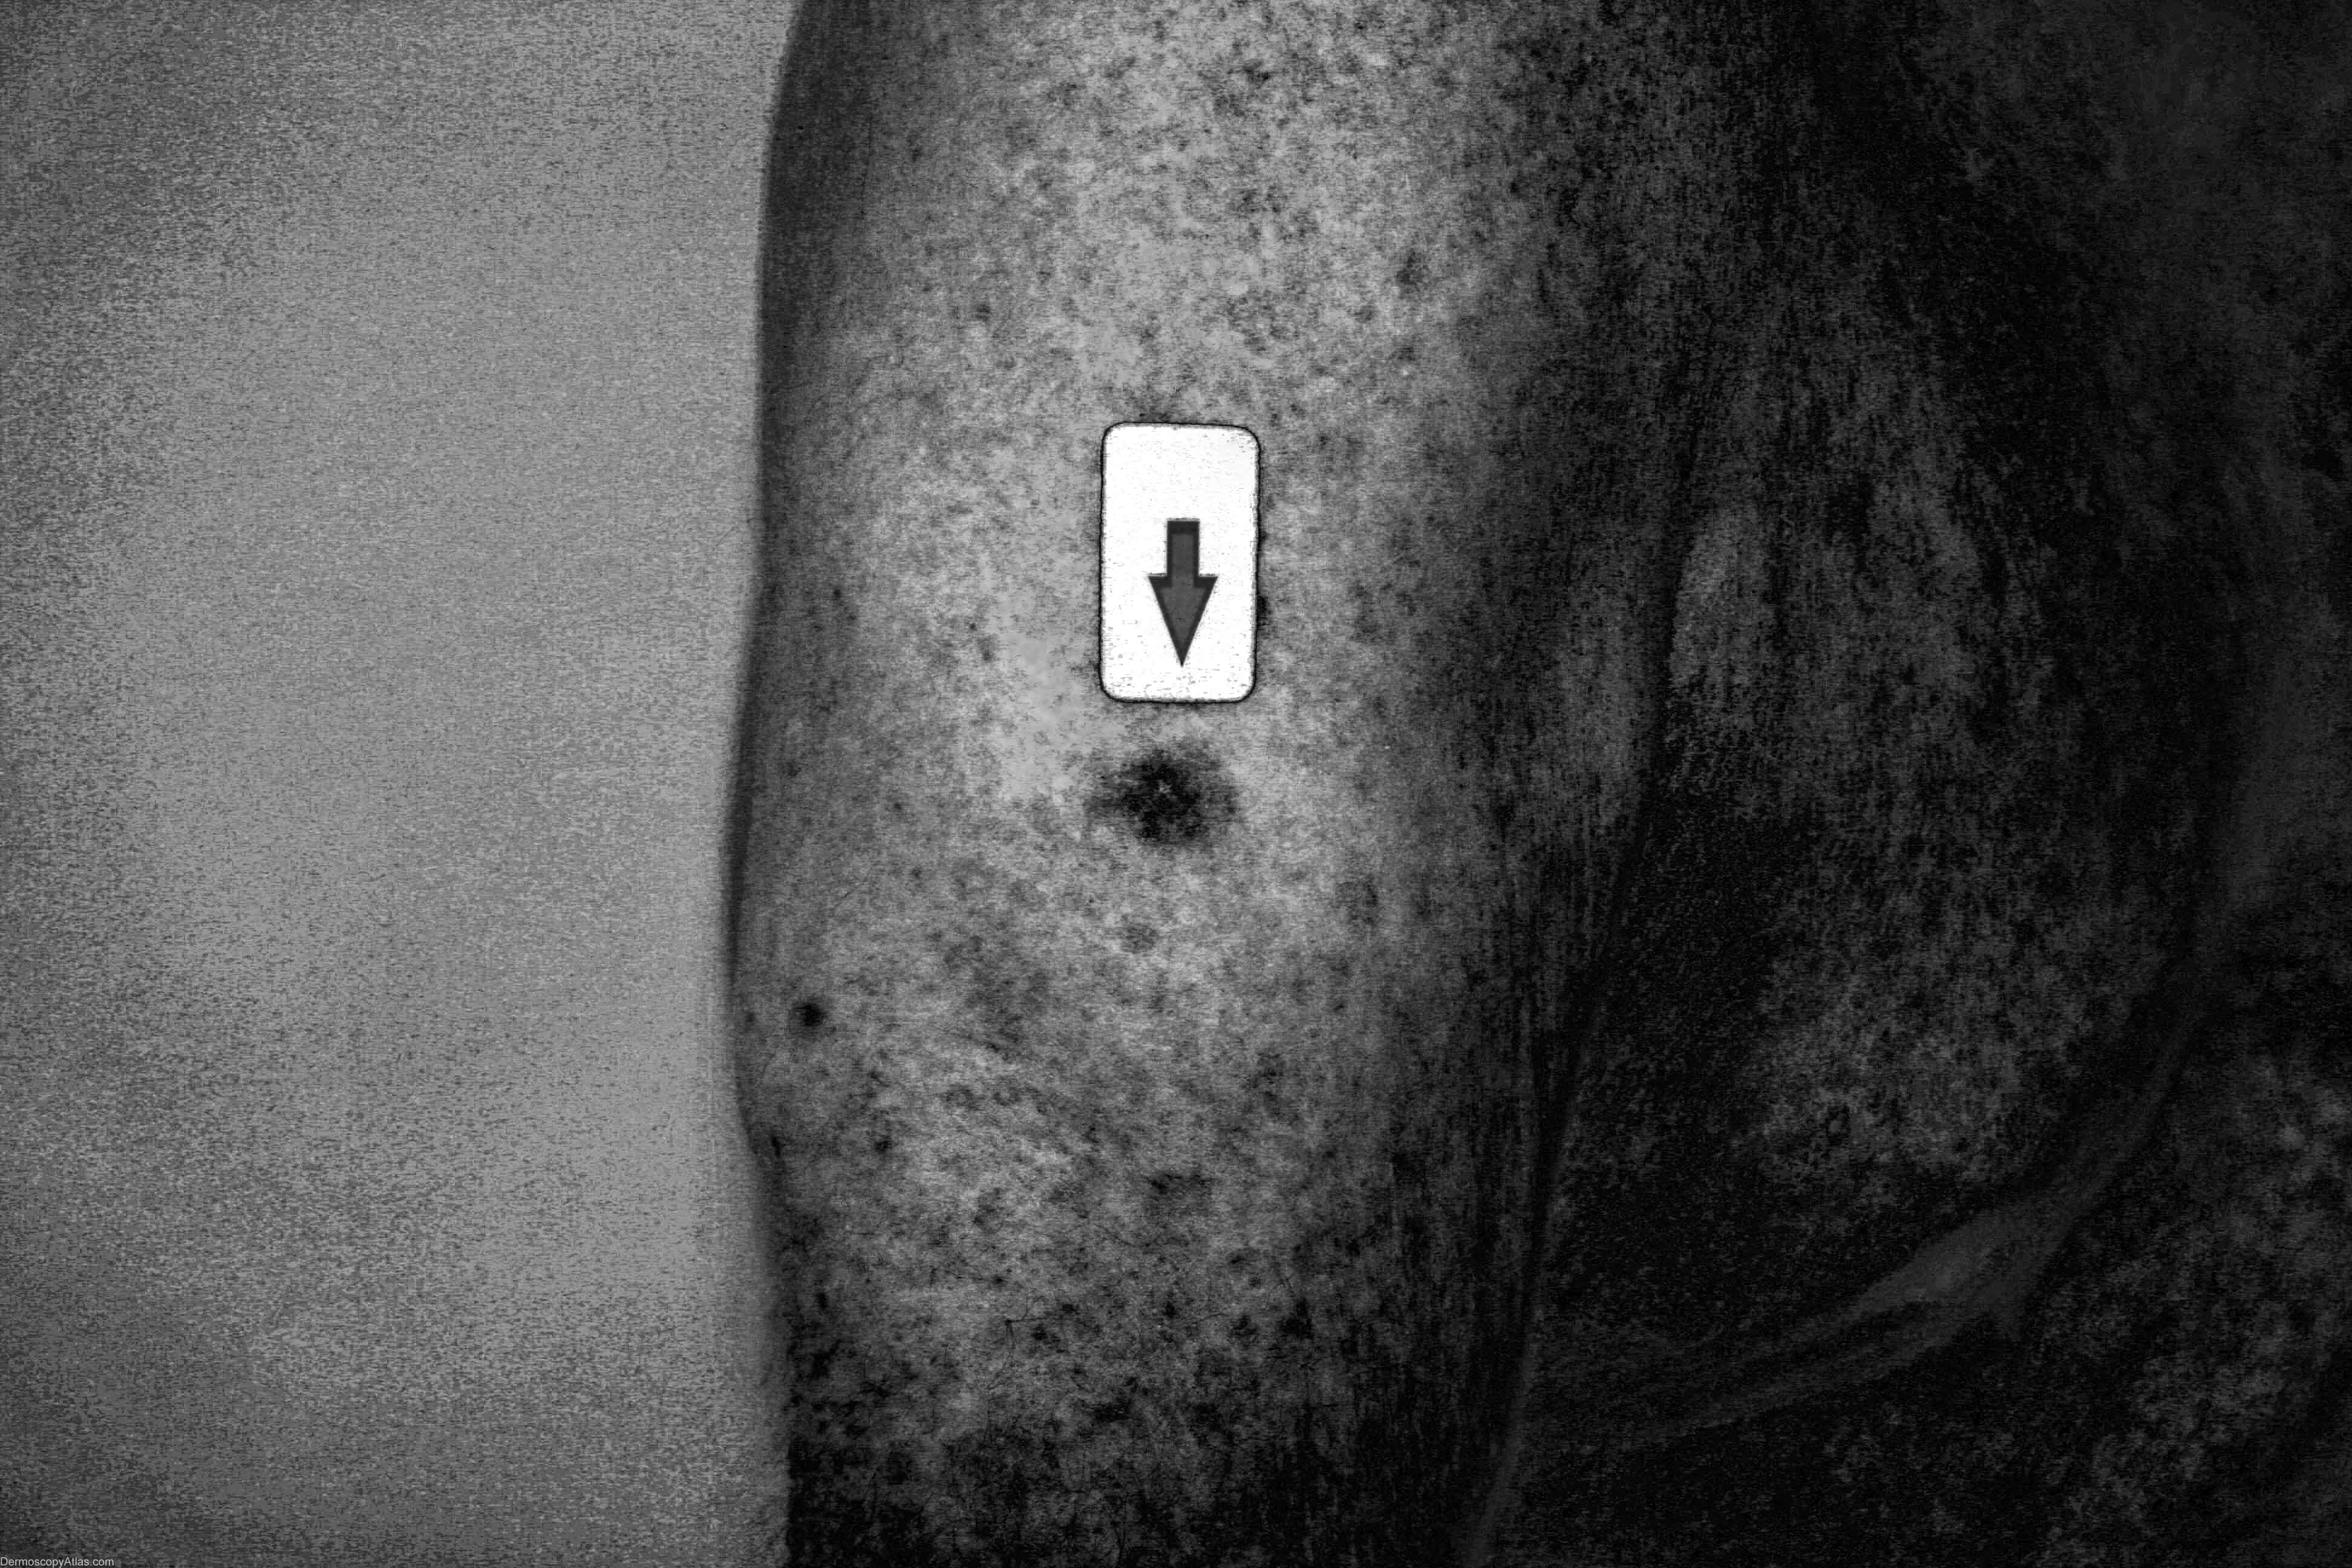

Image Number #2207 (Melanoma amelanotic)

Site: Arm,upper

Diagnosis: Melanoma amelanotic

Description: Clinical image of a small nodule

History: This 87 year old veteran of World War 2 had a regular skin examination ( Past history of non-melanoma skin cancers) and this small papule could not be confidently diagnosed clinically. It was thought to be benign but NMSC needed exclusion. It came back after a 4mm punch biopsy removal of the visible lesion as a level 3 amelanotic melanoma (Breslow thickness 1.3mm) with complete regression of the epidermal component. A further 1.5 cm clearance was obtained and the report came back as superficial spreading amelanotic melanoma (small residual level 2 0.3 mm thick)cleared by only 5mm. In retrospect, especially with enhancement of the image by Dr. Lester Cowell, the large insitu amelanotic melanoma can be visualised.